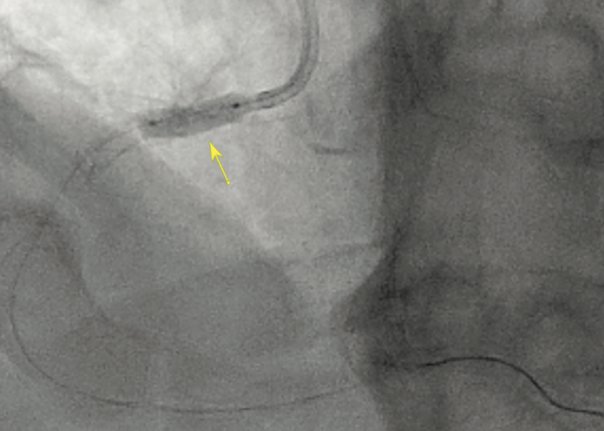

Quiz: Safe and Effective Calcium Modification in Severe Ostial Right Coronary Artery Stenosis

This quiz is based on an interview and case report from Srini Potluri, MD, FACC, FSCAI.

Read "Safe and Effective Calcium Modification in Severe Ostial Right Coronary Artery Stenosis."